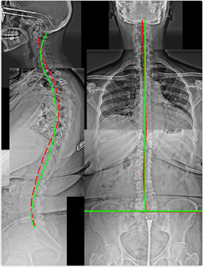

Case 3 — 46yo Male: Chronic Neck & Back Problems

Figure 3. Thoracic Hyperkyphosis, Posterior Thoracic Translation, Anterior Head Translation, Cervical Hypolordosis, Anatomical Leg Length Discrepancy. Leg length discrepancy causes compensatory scoliosis — only confirmed on AP X-ray.